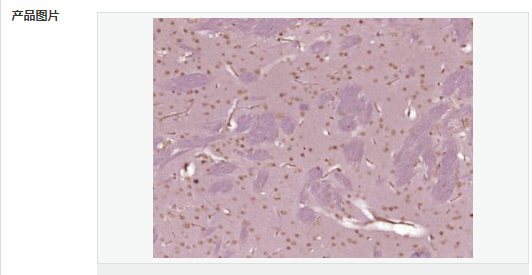

| 產(chǎn)品應用 | ELISA=1:5000-10000 IHC-P=1:100-500 IHC-F=1:100-500 ICC=1:100-500 IF=1:100-500 (石蠟切片需做抗原修復) not yet tested in other applications. optimal dilutions/concentrations should be determined by the end user. |

| 產(chǎn)品介紹 | This gene encodes a protein which contains a hinge region domain found in members of the SMC (structural maintenance of chromosomes) protein family. [provided by RefSeq, Dec 2011] Function: Required for maintenance of X inactivation in females and hypermethylation of CpG islands associated with inactive X. Involved in a pathway that mediates the methylation of a subset of CpG islands slowly and requires the de novo methyltransferase DNMT3B (By similarity). Required for DUX4 silencing in somatic cells. Subcellular Location: Chromosome DISEASE: The disease is caused by mutations affecting the gene represented in this entry. SMCHD1 mutations lead to DUX4 expression in somatic tissues, including muscle cells, when an haplotype on chromosome 4 is permissive for DUX4 expression. Ectopic expression of DUX4 in skeletal muscle activates the expression of stem cell and germline genes, and, when overexpressed in somatic cells, DUX4 can ultimately lead to cell death. Disease description:A degenerative muscle disease characterized by slowly progressive weakness of the muscles of the face, upper-arm, and shoulder girdle. The onset of symptoms usually occurs in the first or second decade of life. Affected individuals usually present with impairment of upper extremity elevation. This tends to be followed by facial weakness, primarily involving the orbicularis oris and orbicularis oculi muscles. SWISS: A6NHR9 Gene ID: 23347 Database links: Entrez Gene: 23347 Human Entrez Gene: 74355 Mouse Omim: 614982 Human SwissProt: A6NHR9 Human SwissProt: Q6P5D8 Mouse Unigene: 8118 Human Unigene: 194450 Mouse Important Note: This product as supplied is intended for research use only, not for use in human, therapeutic or diagnostic applications. |